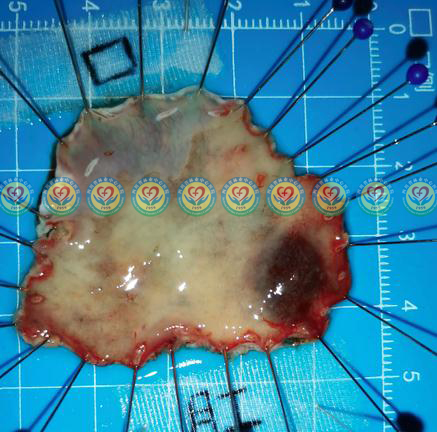

术后标本,病理提示:低级别上皮内瘤变、灶性高级别上皮内瘤变,基底切缘无病变残留、侧切缘无病变残留,为治愈性切除。